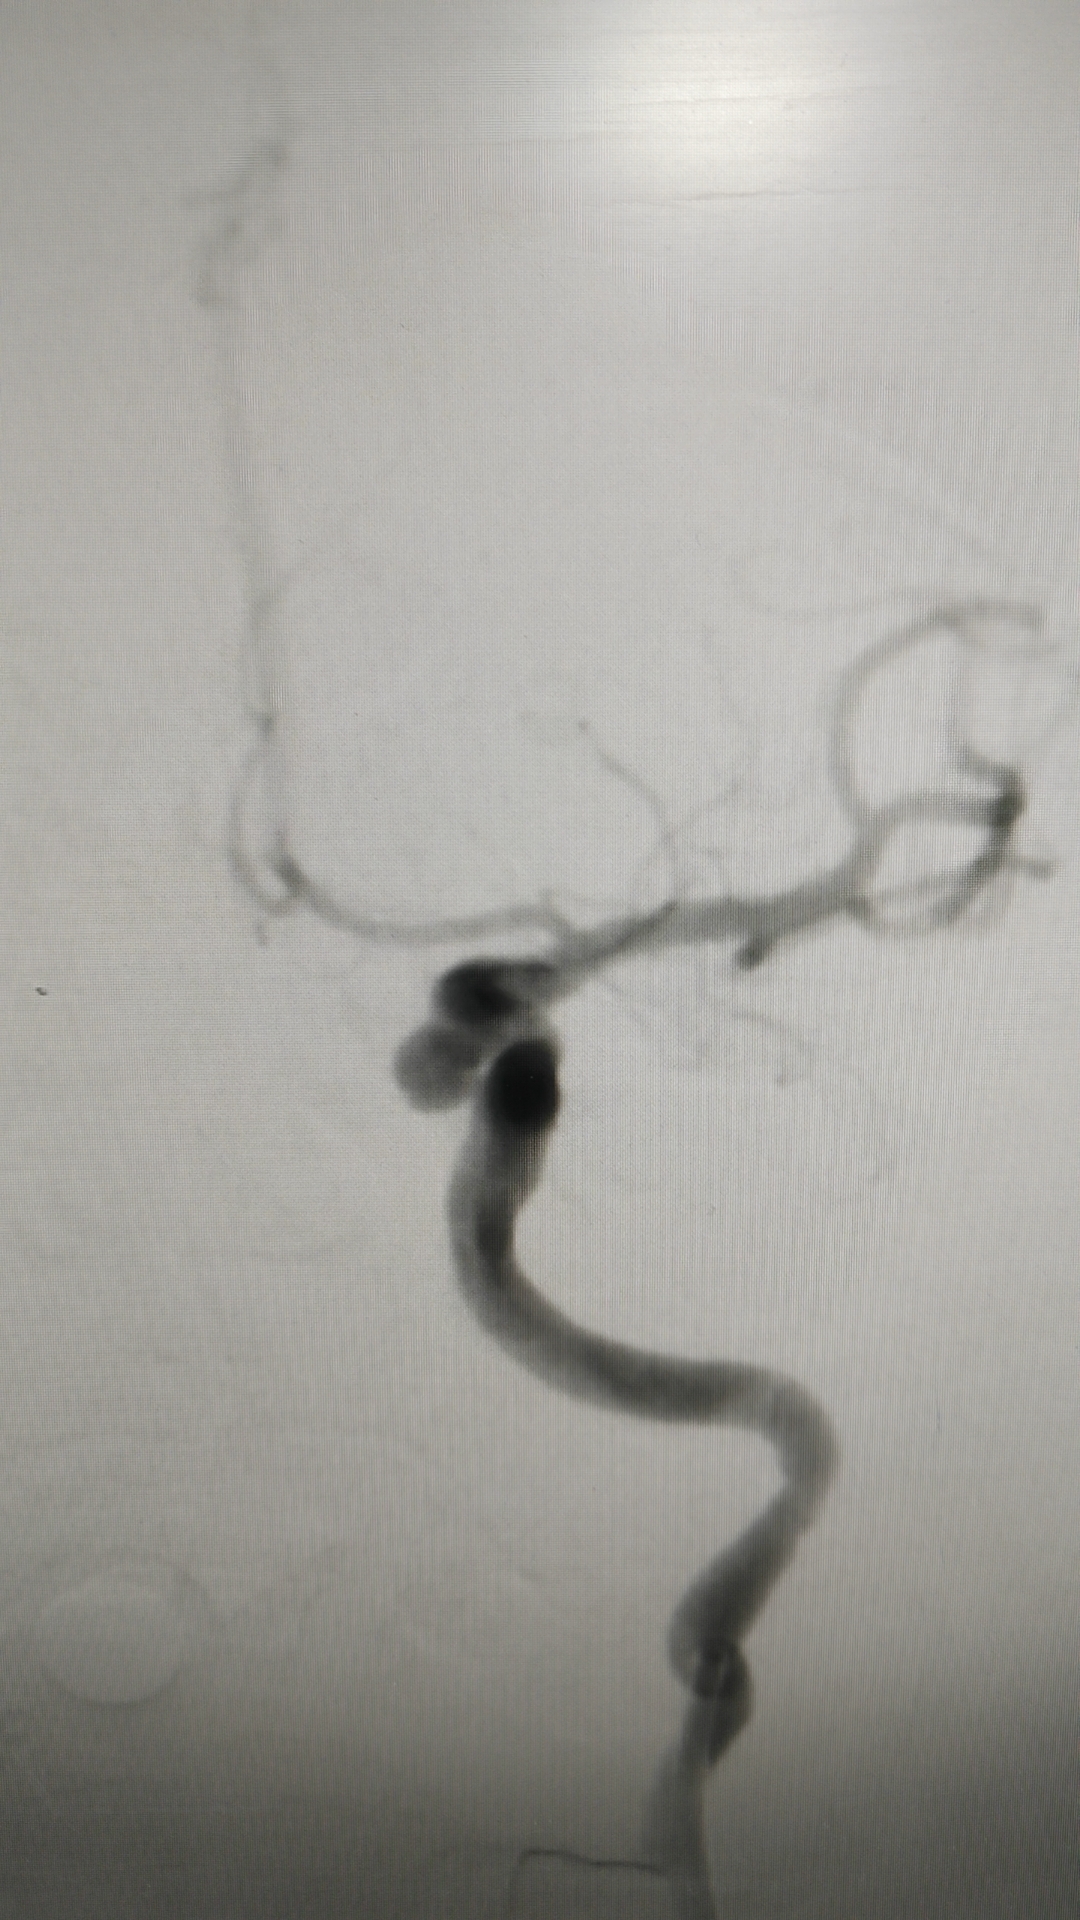

第三次出血后急诊上台,造影显示动脉瘤增大

工作位造影,瘤体约6.1*5.5mm,更加确认是血泡样动脉瘤!

3D成像!